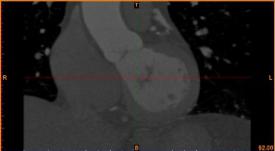

首先通過病人的心臟冠脈造影CT數據,獲取病人的心臟冠脈三維模型。

病人的冠脈造影CT數據 提取出的冠脈三維數據